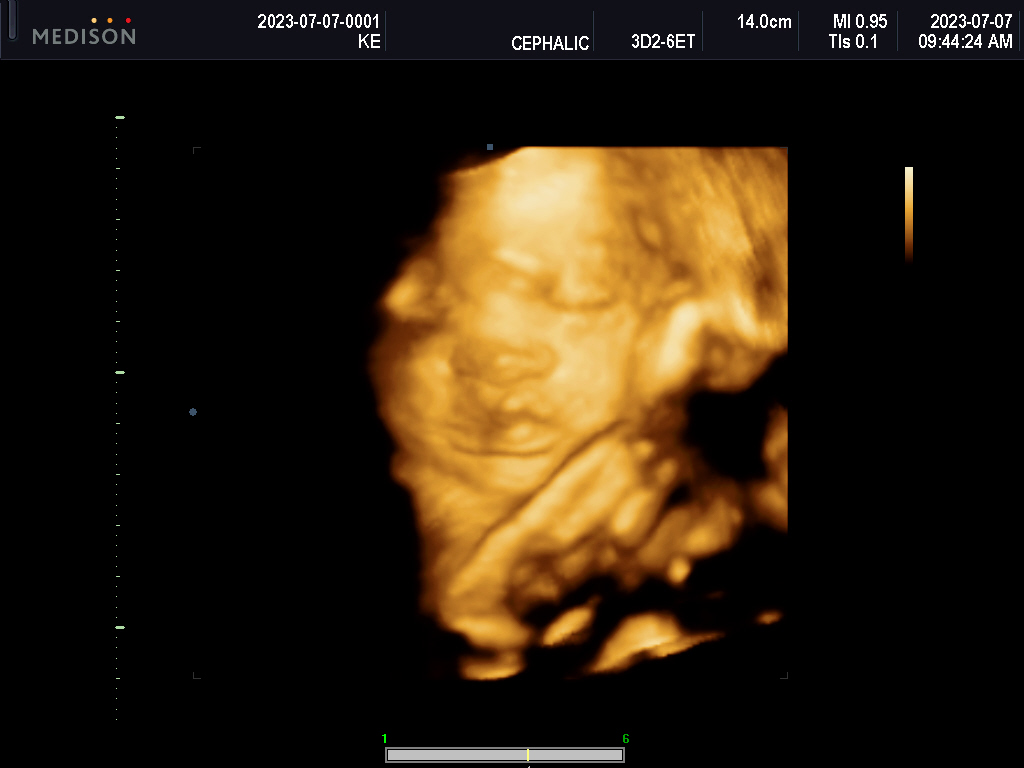

What will she look like?

What parts of us will she carry?

Will she have Nono’s forhead? FIFI’s stubbornness?